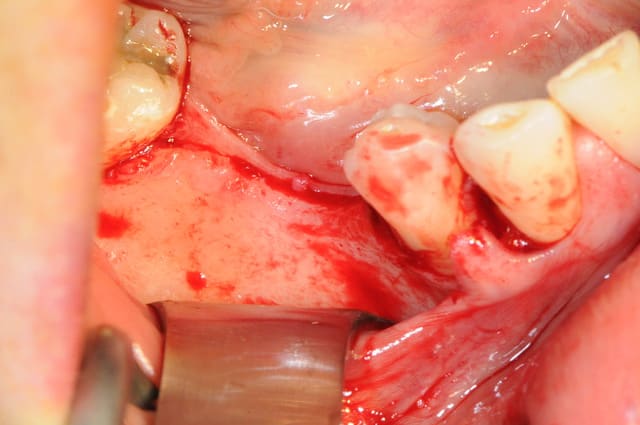

voici l'un des secrets pour une bonne réussite dans ce type d'intervention.

il faut absolument que les berges de la gencive n'aient aucune tension. donc il faut quelques points de chaipuki (photo1) puis réaliser la fermeture des berges (photo2)

les derniers fils peuvent être alors très fins (ici du 6/0)